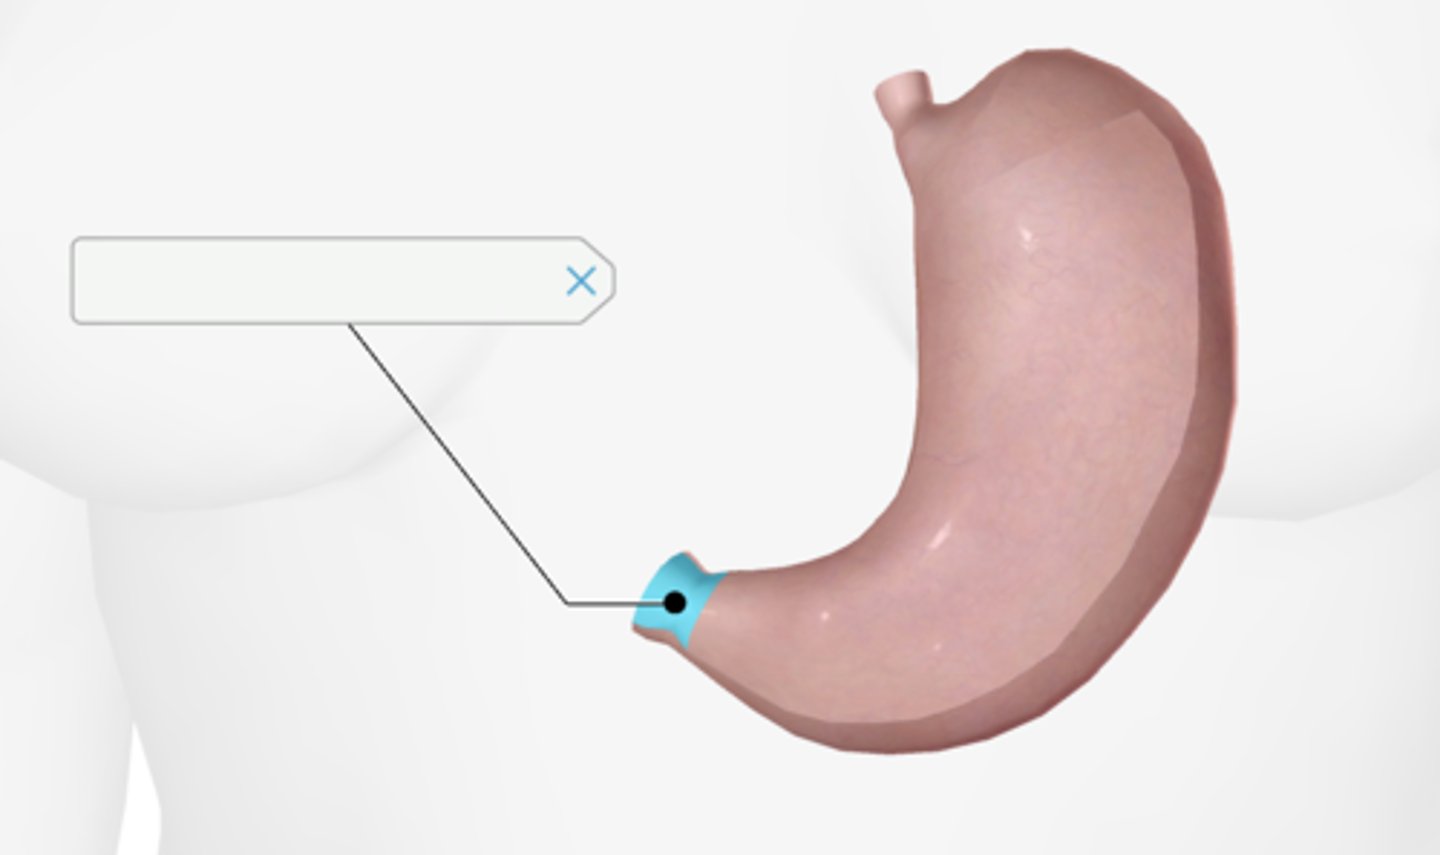

Pyloric sphincter